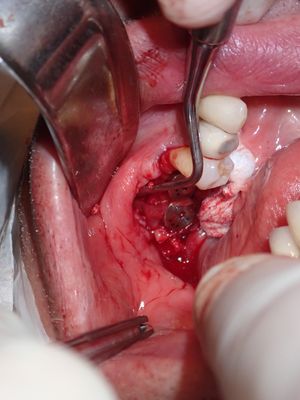

large amount of bone loss at time of exo 36/37 done 2 months ago. Good healing of bone except for small socket area at 36 region. buccal bone lower than palatal about 1mm, decided to place tissue level implants opposed to grafting, gaining back height is unlikely, difficult access case with large tongue. Implants placed with 36 about 1.5mm buccal exposed, 37, .5mm mesial exposed, healing abutments palced grafted all sites with sticky bone followed by collagen membrane soaked in prf fluid, 2 holes cut for implants. additonal fibrin membrance placed on buccal prior to suturing.